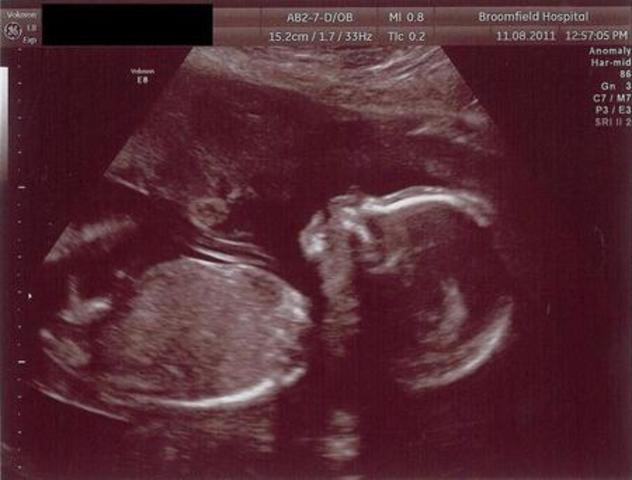

SEMANA 28

Su piel dejó de ser transparente porque se depositó queratina. Los pulmones comienzan a producir surfactante, sustancia imprescindible para el inicio de la respiración Sus periodos de vigilia son más prolongados..